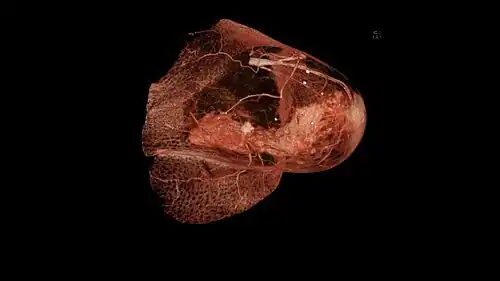

Nach der Operation wird das aus der Brustdrüse entfernte Operationspräparat in der histologischen Untersuchung auf seine exakte Größe gemessen und das Gewebe auf weiteren Befall untersucht. Die entfernten Lymphknoten werden auf Metastasen geprüft. Die Größe des Karzinoms und die Anzahl der befallenen Lymphknoten sind für die TNM-Klassifikation, Prognose und weitere Behandlung von Bedeutung. Das Operationspräparat wird auch daraufhin vermessen, ob der Abstand zwischen dem Karzinom und dem verbliebenen, gesunden Gewebe ausreichend groß ist. Sollte dies nicht der Fall sein, kann eine Nachoperation nötig werden, damit ein angemessener Sicherheitsabstand zwischen gesundem und erkranktem Gewebe erreicht wird.